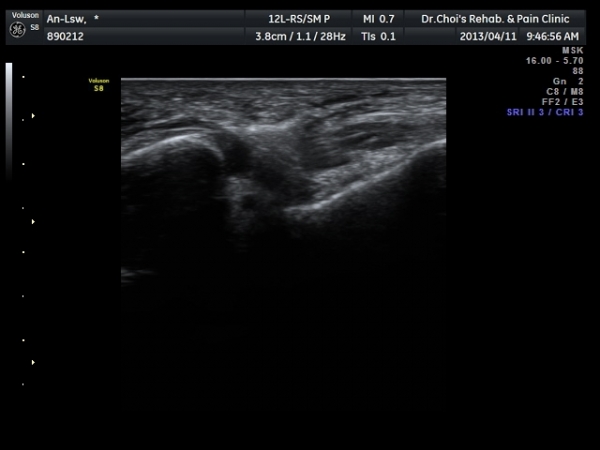

Àü°Å°ñºñ°ñÀδë Á¾´Ü¸é°Ë»ç»ó Àδë ÀδëÀÇ Àú¿¡ÄÚ ºÎÁ¾°ú(±×¸² 3)

ºñ°ñºÎÂøºÎ ¿¬°á¼º ¼Ò½ÇÀÌ °üÂûµÈ´Ù(±×¸² 4).

ÃÊÀ½ÆÄÅõ½ÃÇÏ ºÎÇϰ˻翡¼­ ºñ°ñ°ú ÀÎ´ë ºÎÂøºÎ¿Í ºñ°ñ°ú °Å°ñ »çÀ̰¡ ¹ú¾îÁø´Ù

(樨毢 1)